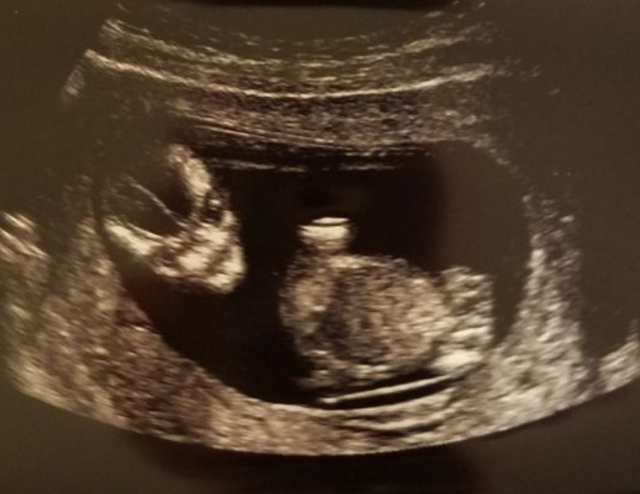

13週6日(13w6d・女の子)|toa さん(28歳)

エコー写真撮影時のエピソード:

初めて4Dでエコーを撮った時のものです。 なかなか顔を見せてくれなかったのですが助産師さんの与えた刺激に反応しちょっと動いて俯き加減の横顔が見えました。

good luckと言っているようなこのポーズに盛り上がりました。